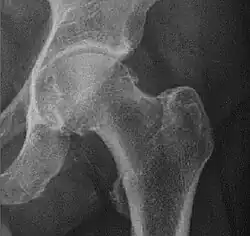

Measurements

- Fossa/ilioischial relationship: In normal conditions the floor of the acetabular fossa is lateral to the ilioischial line by 2 mm in men and 1 mm in women. When the acetabular floor overlaps or overpasses the ilioischial line, the diagnosis of coxa profunda can be made. Nevertheless, coxa profunda had been found in 76% of asymptomatic hips, mainly in women. Therefore, this as an isolate criterion is not enough to make the diagnosis of pincer-type impingement. A more severe condition is protrusio acetabuli, diagnosed when the femoral head overlaps or overpasses the ilioischial line.[3]

- Joint space: In the adult hip, normal joint space ranges from 3 to 5 mm and must be uniform. Values under 2 mm are consistent with joint space narrowing.[3]